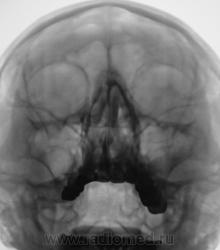

Пристеночное утолщение слизистой, выроженный отек носовых ходов - картина риносинуита.

А округлый контур затемнения в левой гайморовой пазухе не киста? Утолщение слизистой носа.

На кисту, судя по контуру и по объему затемнения не похоже, больше данных за отек, реком-ся контроль в динамике (через 3-4 недели) -отек "уйдет", а оценивать состояние слизистой носа - привилегия ЛОР-врачей

в левой гайморовой пазухе отек слизистой, в альвеолярной бухте просится пломбировочный материал. хорошо бы панорамную томографию или дентальный снимок, или гайморография в прямой и левой боковой проекциях

Состояние двузначное:с одной стороны есть как бы некоторое заокругление верхнего контура и локальность поражения; с другой - вытянутость формы затемнения, но, опять же таки - локальность. Т.е., с одной стороны локальность больше характерна для кисты, но не совсем, мягко говоря, характерна для гайморита. Как бы там ни было - клиент для КТ, цель - уточнение состояния слизистой.